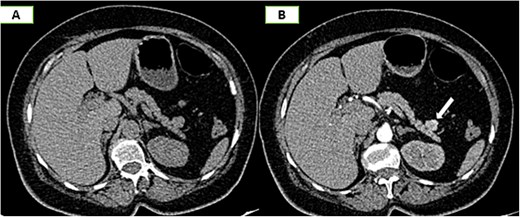

On the complementary CT scan, this lesion exhibits the same tissue characteristics and enhancement as the spleen (Fig. 2), along with its own vascularization through a distinct vascular pedicle (Fig. 3), which is more suggestive ‘of an accessory spleen than an insulinoma of the tail of the pancreas.’

Axial sections of an abdominal CT scan in the arterial phase (A) and vascular reconstructions (B) demonstrate the vascularization of the accessory spleen through its pedicle.

In our patient, the CT scan played an important role in characterizing the lesion located in the tail of the pancreas, supported by the following arguments:

Arterial enhancement within the lesion, resembling that of the spleen and reminiscent of the zebra-stripe pattern.

The identification of a vascular pedicle supplying the accessory spleen (Fig. 3).

This allowed us to make the diagnosis of an accessory spleen adjacent to the tail of the pancreas instead of that of an insulinoma.